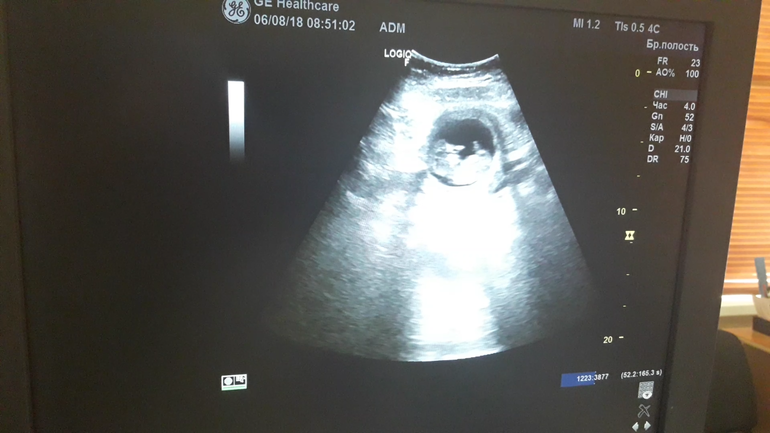

УЗИ 12я неделька! Растем)))

Не по дням, а по часам))) КТР - 45, БПР - 19. Все в пределах нормы))) Манюся, мы тебя ждем))